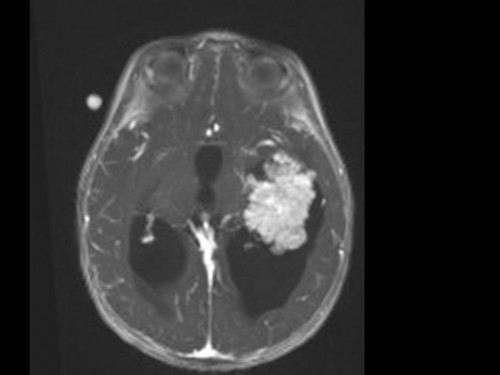

10 Monate altes Mädchen. Der Kinderarzt stellt fest, dass das kleine Mädchen einen recht großen Kopfumfang hat, nicht mit den Augen fixiert und anscheinend auch nicht richtig sehen kann. Damit bestätigt er die größten Befürchtungen der Eltern, denen in den letzten Wochen aufgefallen war, dass ihre Tochter nach keinem Spielzeug mehr greift und sie nur dann anlächelt, wenn sie zu ihr sprechen.

Bildgebung - MRT